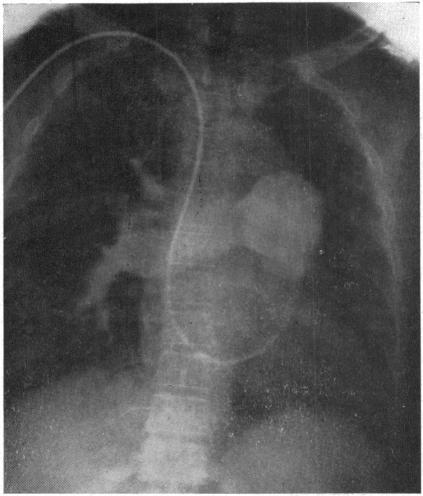

CHESLER E, DUCKWORTH W C

Br Heart J. 1964 Sep;26(5):705-8. doi: 10.1136/hrt.26.5.705.